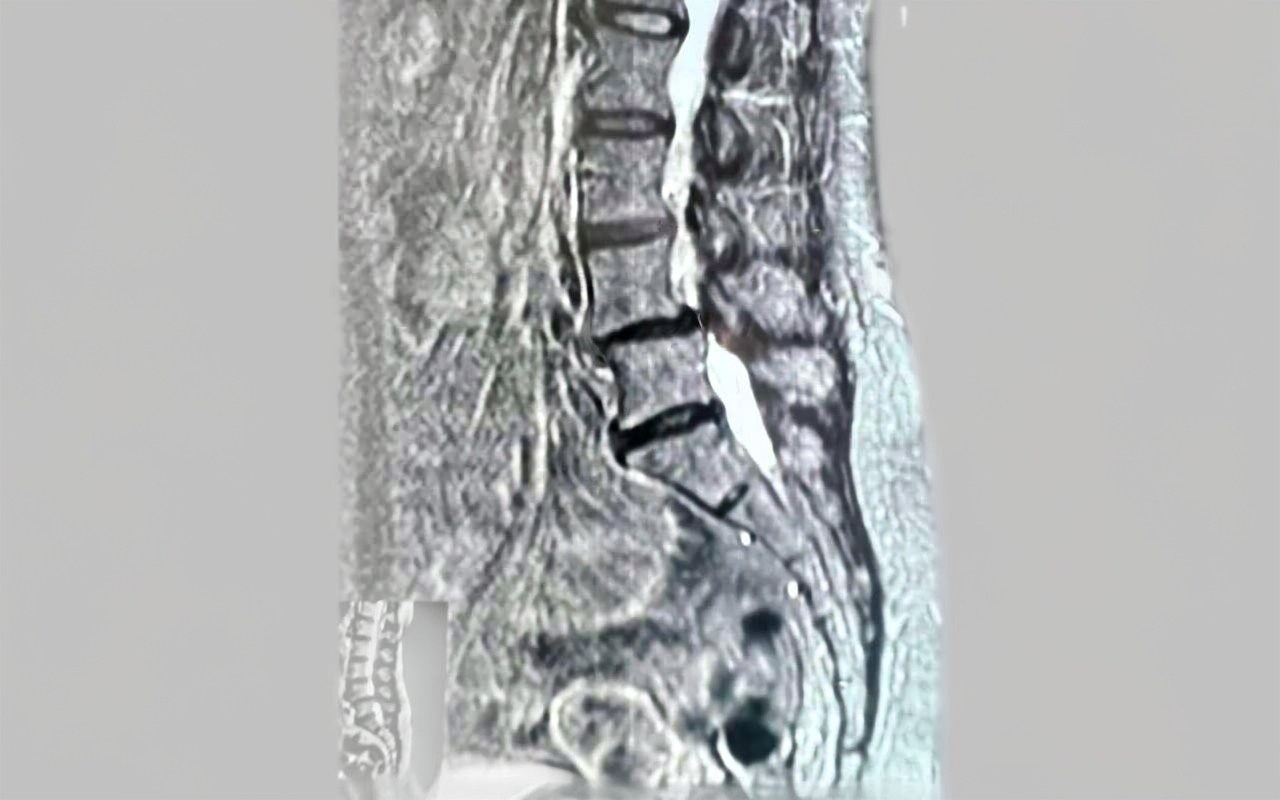

Пациентка поступила в отделение с жалобами на боли в пояснице и ногах, онемение и трудности при ходьбе, которые не поддавались консервативному лечению в течение года. Обследование выявило ряд патологий, включая поражение межпозвоночных дисков и сужение позвоночного канала.

Хирурги выполнили декомпрессивно-стабилизирующую операцию, в ходе которой удалили грыжу и повреждённые диски, заменили их имплантами, сняли давление на спинной мозг и нервы с помощью микрохирургической техники. Также был исправлен смещённый позвонок и установлена конструкция для его стабилизации.